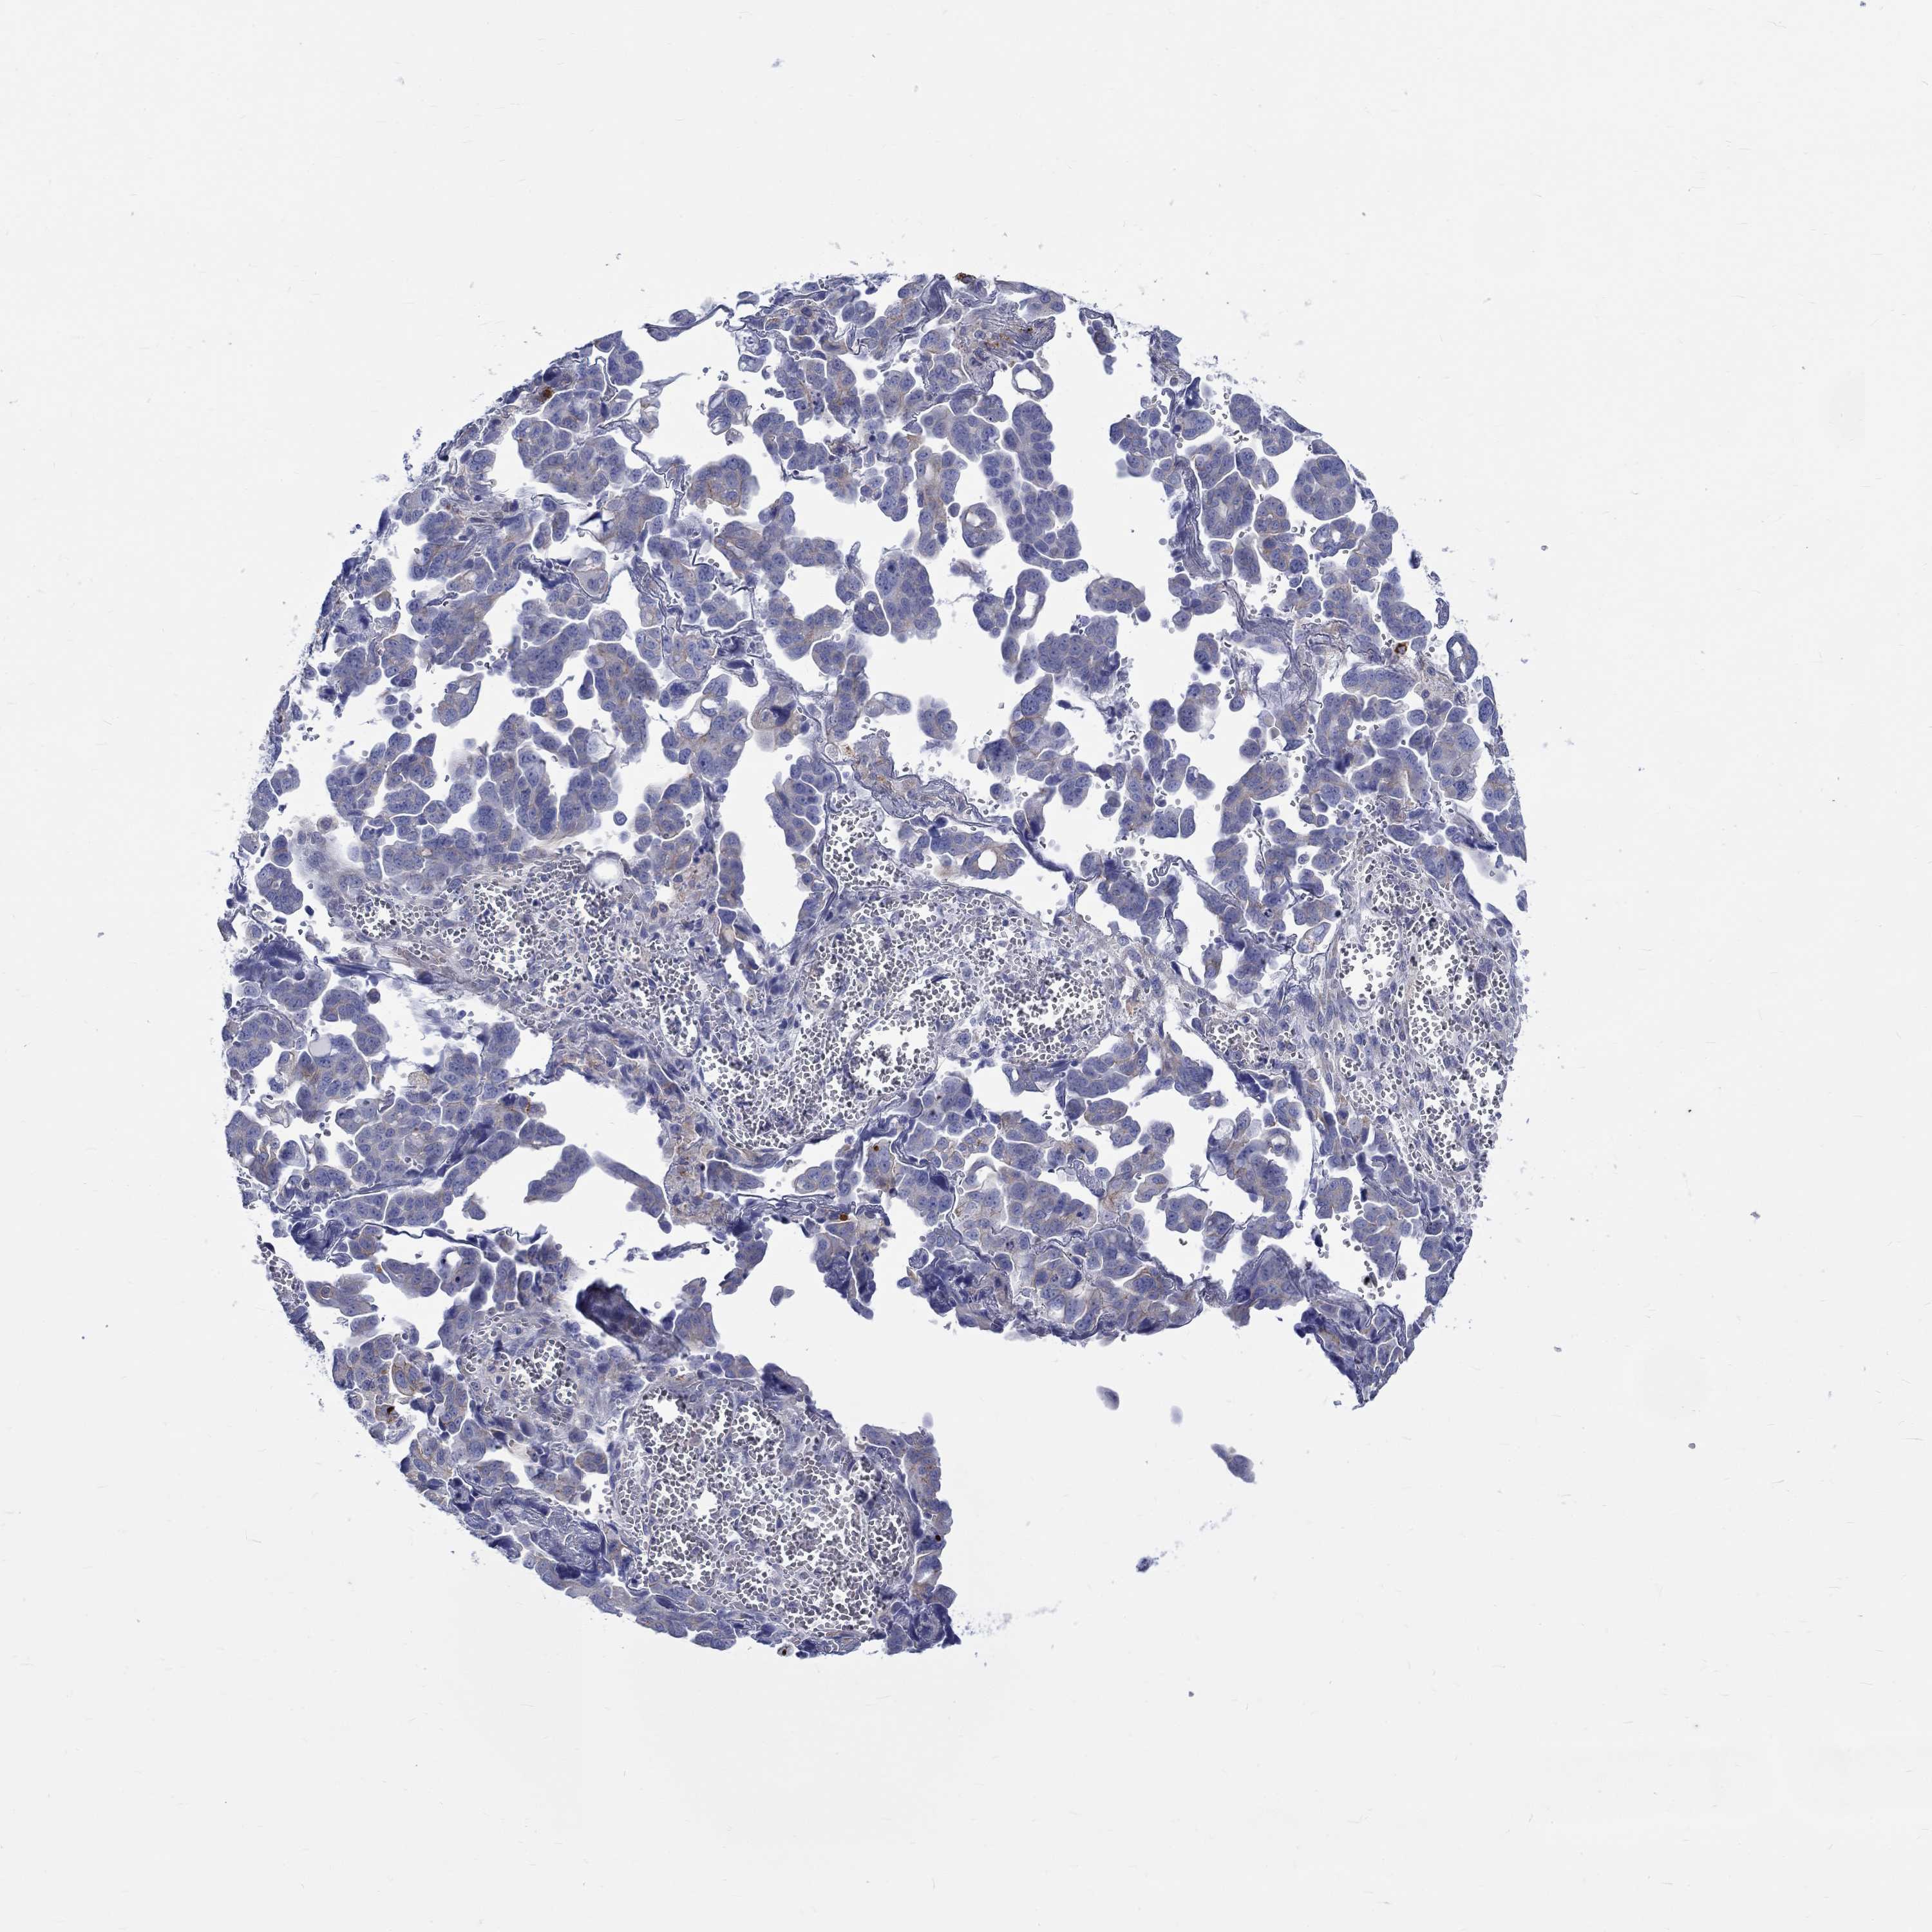

OVARIAN CANCER - Protein expressioni

A mouse-over function shows sample information and annotation data. Click on an image to view it in a full screen mode. Samples can be filtered based on level of antibody staining by selecting one or several of the following categories: high, medium, low and not detected. The assay and annotation is described here.

Note that samples used for immunohistochemistry by the Human Protein Atlas do not correspond to samples in the TCGA dataset.

Antibody stainingi

Antibody staining in the annotated cell types in the current human tissue is reported as not detected, low, medium, or high, based on conventional immunohistochemistry profiling in selected tissues. This score is based on the combination of the staining intensity and fraction of stained cells.

Each image is clickable and will lead to virtual microscopy that enables deeper exploration of all samples and also displays staining intensity scores, fraction scores and subcellular localization as well as patient and tissue information for each sample.

Antibody HPA076728

Staining

High

Medium

Low

Not detected

Intensity

Strong

Moderate

Weak

Negative

Quantity

>75%

75%-25%

<25%

None

Location

Nuclear

Cytoplasmic/membranous

Cytoplasmic/membranous,nuclear

Cystadenocarcinoma, serous, NOS

Cystadenocarcinoma, mucinous, NOS

Carcinoma, endometroid